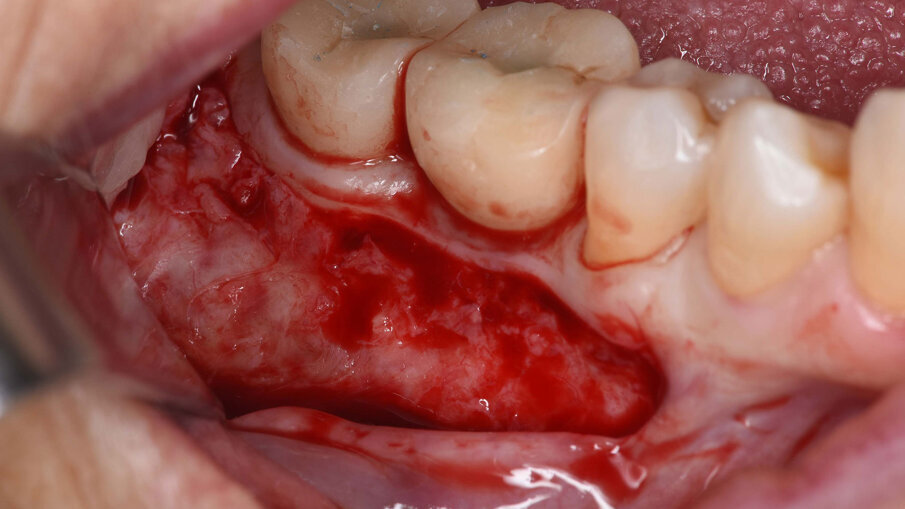

Il prelievo di osso autologo particolato è stato eseguito dal ramo mandibolare, distalmente alla zona da ricostruire mediante uno scraper (SafeScraper Twist, META). La griglia è stata provata nel sito ricevente per verificarne la congruità. Ogni residuo di tessuto connettivo è stato rimosso; per aumentare la rivascolarizzazione precoce del materiale innestato, sono state eseguite delle perforazioni della corticale ossea del sito ricevente (Figg. 3, 4). Dopo preparazione dei siti implantari, sono stati posizionati due impianti “root form” e “bone level” in zona 4.6 e 4.7 (4.1 x 8 mm; Straumann) usando una dima chirurgica. La griglia è stata quindi riempita con un mix di osso autologo ed eterologo (Geistlich Bio-Oss, Gestlich Pharma) in rapporto 1:1, è stata fissata con 3 micro-viti in titanio di 1.4 mm di diametro (MC Bio) ed è stata ricoperta con una membrana riassorbibile (Geistlich Bio-Gide, Gestlich Pharma; Figg. 5, 6). La sutura è stata eseguita per prima intenzione (Fig. 7).

Fig. 4_Visione intra-operatoria della griglia posizionata nel sito da rigenerare e che mostra il difetto osseo prima del suo riempimento.